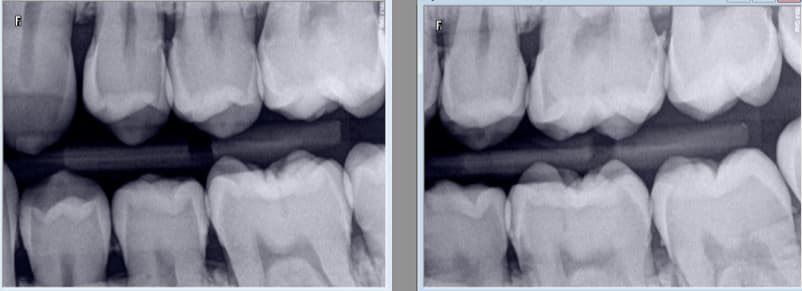

Ici radiographies de 4 secteurs centrés sur 25 26 35 36. -)

(18, 17, 16) (15, 14, 13) ( 12, 11, 21) (22, 23,24) ( 25,26,27)

Vous n'optimisez pas vos clichés mon cher. Mes secteurs de 3 dents contigus sont bien DISTINCTS pas les vôtres. -)

Par contre heureusement tu as fait 2 secteurs et des radios il en faut au moins 2. -)

HBQK191 Radiographies intrabuccales rétroalvéolaires et/ou rétrocoronaires de 2 secteurs distincts de 1 à 3 dents contigües